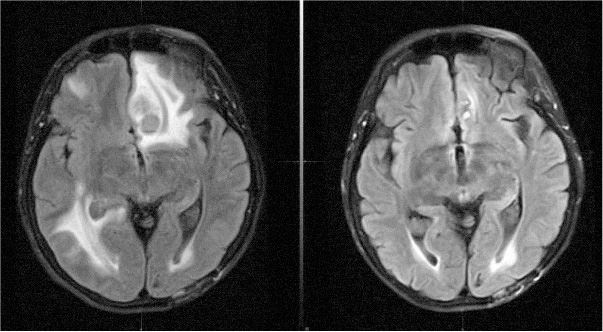

Снимки моего мозга 19 июня (слева) и 21 июля (справа). Отек (светлые области на снимке) заметно спал, и опухоли, включая самую крупную во фронтальной коре, исчезли